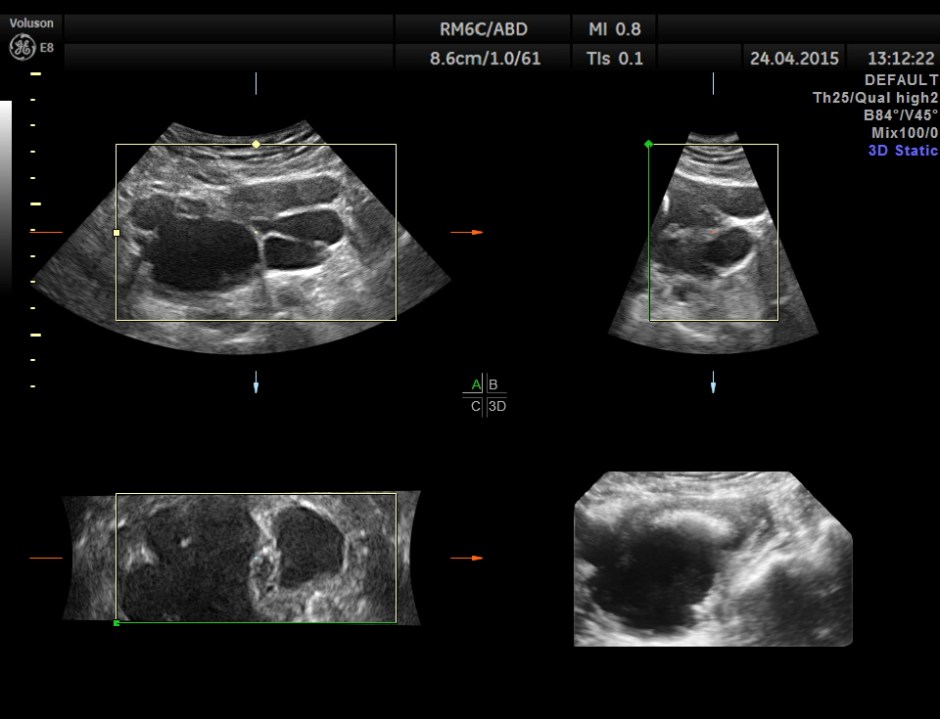

Scan of the urinary bladder in a more cephalic angle shows the following :

Superior angling shows a multi cystic pelvic mass – ? bladder diverticulae